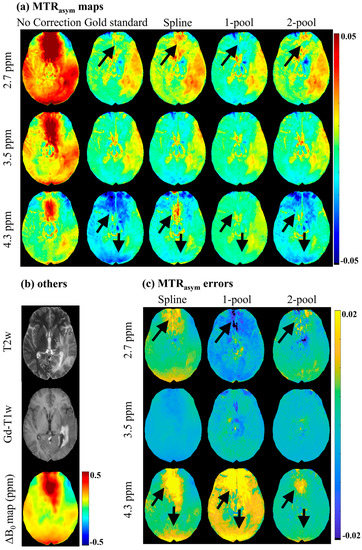

Figure 2 shows the MTRasym maps and the corresponding error maps of a representative brain tumor patient. As seen in Figure 2a, before B0 correction, MTRasym maps had severe B0 artifacts, which would have influenced the identification and analysis of tumors (as shown in Figure 2b), especially for 2.7 ppm. The spline-based correction method alleviated some B0 artifacts; however, in the regions with high B0 inhomogeneity (ΔB0 > 0.5 ppm), the artifacts still appeared on MTRasym (2.7 ppm) and MTRasym (4.3 ppm). The one-pool Lorentzian-based method seemed to eliminate artifacts in regions with high B0 inhomogeneity, but generated wrong MTRasym (4.3 ppm) maps, which were quite different from the gold standard. Compared with the maps generated using the spline and one-pool methods, the three MTRasym maps corrected using the proposed two-pool Lorentzian-based method not only were more similar to the gold standard, but also had fewer B0 artifacts. This can also be validated by the MTRasym error maps, shown in Figure 2c. Using our method, there were fewer MTRasym errors of limbic offsets than when using the spline and one-pool methods, especially in the regions with relatively high B0 inhomogeneity. The MTRasym maps and MTRasym error maps of a representative healthy volunteer are shown in Figure S2 in the Supplementary Materials.

Figure 2. MTRasym maps and MTRasym error maps of a representative brain tumor patient. (a) MTRasym maps without B0 correction, gold standard, and MTRasym maps corrected using spline, 1-pool Lorentzian and 2-pool Lorentzian methods; (b) T2w, Gd-T1w and ΔB0 map; (c) the corresponding MTRasym error maps with gold standard.